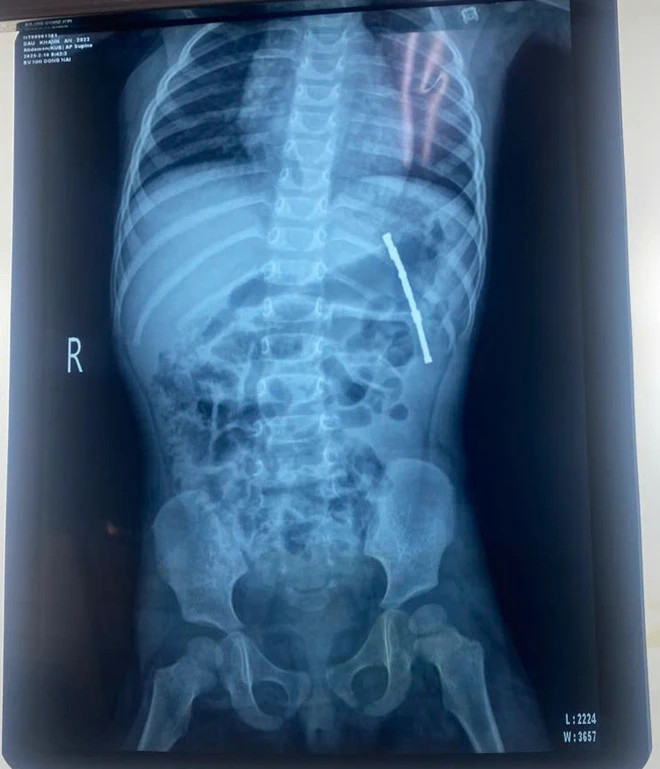

Bệnh nhân được chỉ định chụp x-quang bụng và phát hiện có nhiều dị vật trong đường ruột. Các bác sĩ đã tiến hành nội soi dạ dày cấp cứu tại phòng mổ và thấy có một khối nam châm khoảng 11 viên nhỏ (kích thước khoảng 3mm mỗi viên) đang dính chặt vào nhau và dính chặt vào mặt dưới dạ dày.

| Dị vật nam châm trên phim chụp - Ảnh BVCC |

Sau mổ hở, bác sĩ nhận thấy có 3 lỗ thủng các vị trí lần lượt ở mặt dưới dạ dày và 2 lỗ thủng ở ruột non. Qua các lỗ thủng này, bác sĩ lấy ra thêm 17 viên nam châm nhỏ. Tổng cộng, có 27 viên nam châm đã được lấy ra với tổng chiều dài khoảng 4-5cm, vài viên có dấu hiệu rỉ.